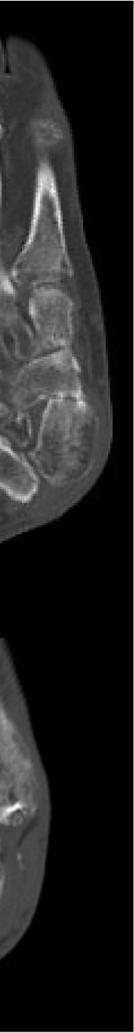

921 Charcot Neuroarthropathy of the Foot and Ankle in the Acute Setting: An Illustrative Case Report and Targeted Review

Kian Bagheri, Albert T. Anastasio, Alexandra Krez, Lauren Siewny, Samuel B. Adams